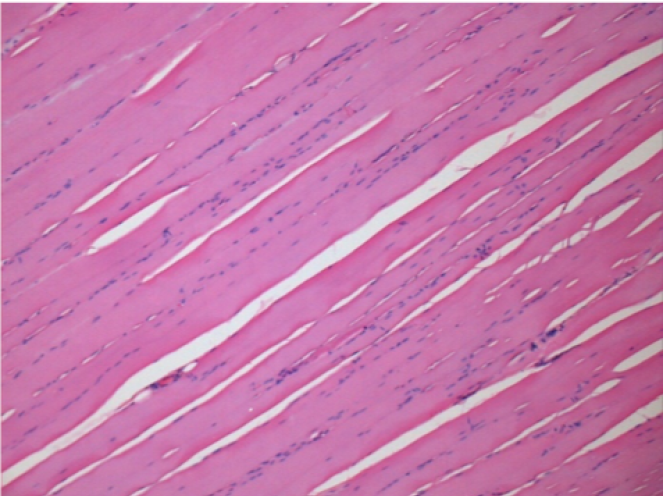

L:Pretibial-No treatment